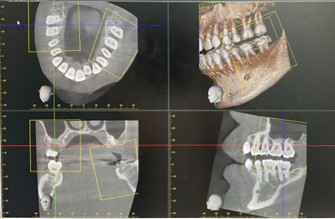

高精細な3D画像が撮影可能な『歯科用CT』

副鼻腔から歯根の形態、顎関節まで詳細に評価でき、幅広い診断・治療に対応可能です。

副鼻腔症状の診断

炎症や病変の広がりを正確に把握

顎関節症の診断

関節の骨構造(変形や吸収の有無)を詳細に把握